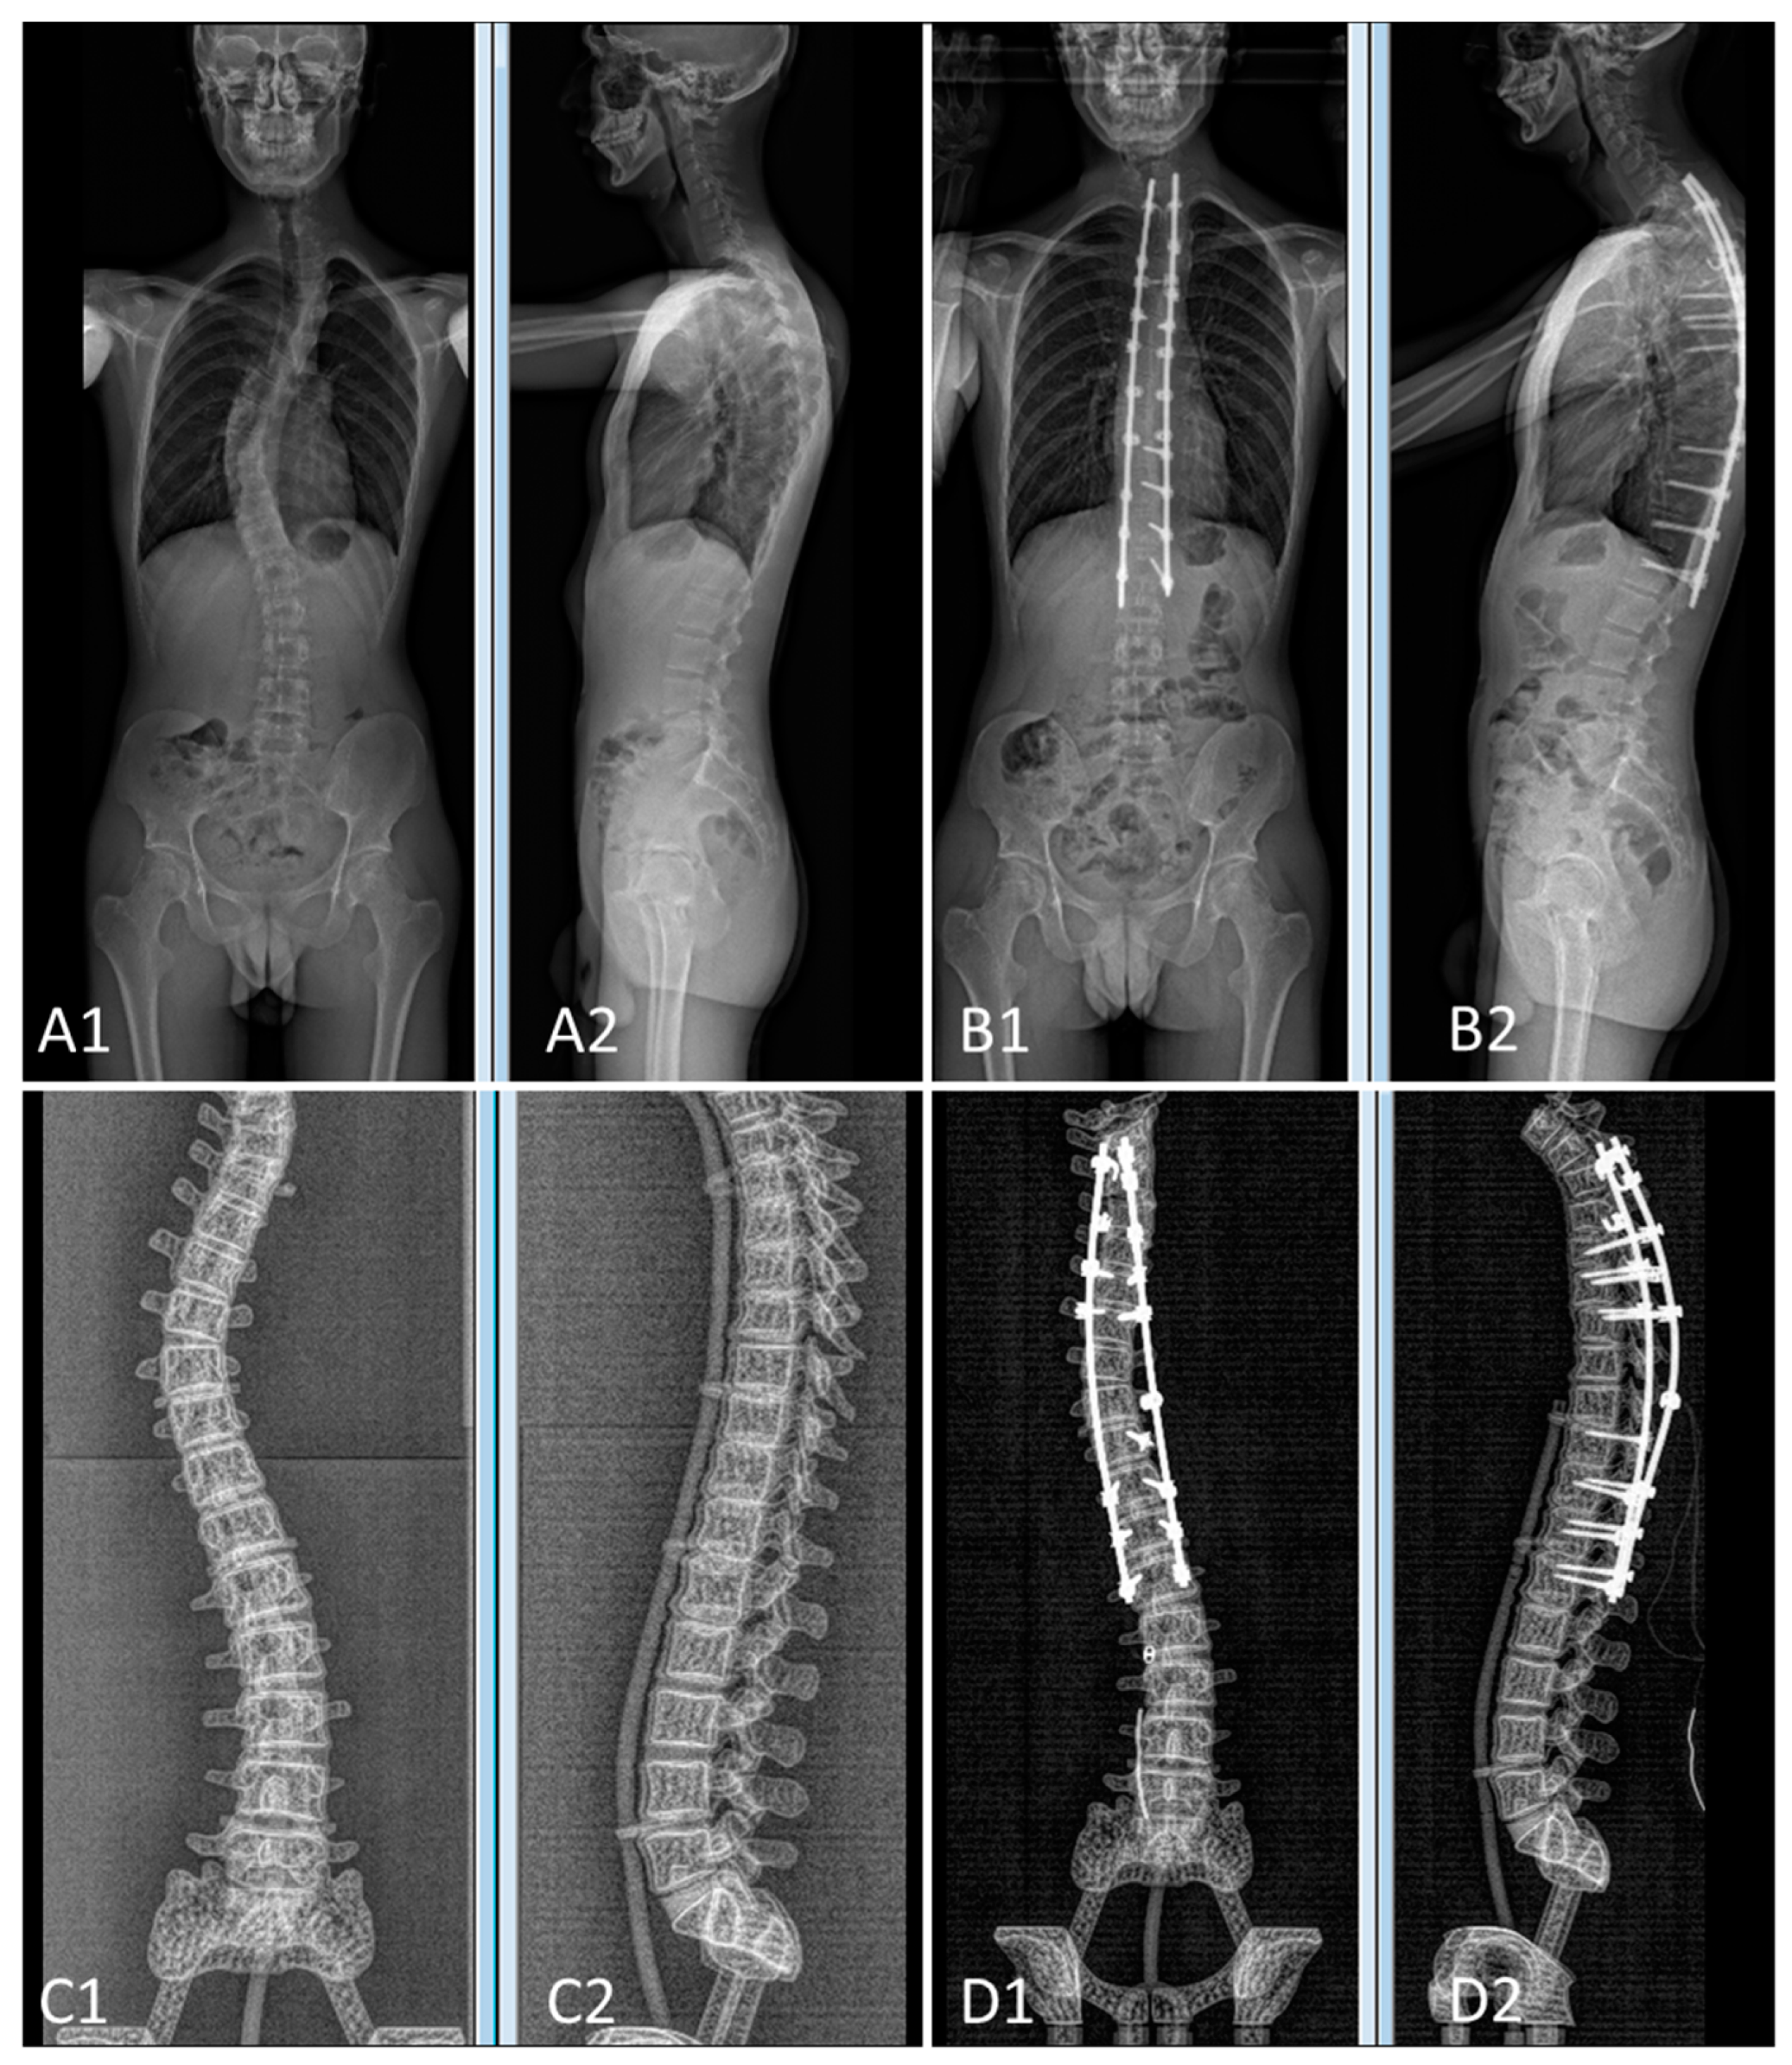

The pre- and postoperative constructs of one of the 3D-printed spine twins can be seen in Figure 9. Figure 8 (Patient 1) and Figure 10 (Patient 2) demonstrate pre- and postoperative bi-planar X-rays of the actual patient and their 3D-printed twin spine.

Figure 10. Bi-planar X-rays of patient 2 and 3D-printed twin 2. (A): Preoperative X-rays of patient 2 ((A1): frontal view, (A2): lateral view). (B): Postoperative X-rays of patient 2 ((B1): frontal view, (B2): lateral view). (C): Preoperative X-rays of 3D-printed twin 2 ((C1): frontal view, (C2): lateral view). (D): Postoperative X-rays of 3D-printed twin 2 ((D1): frontal view, (D2): lateral view).